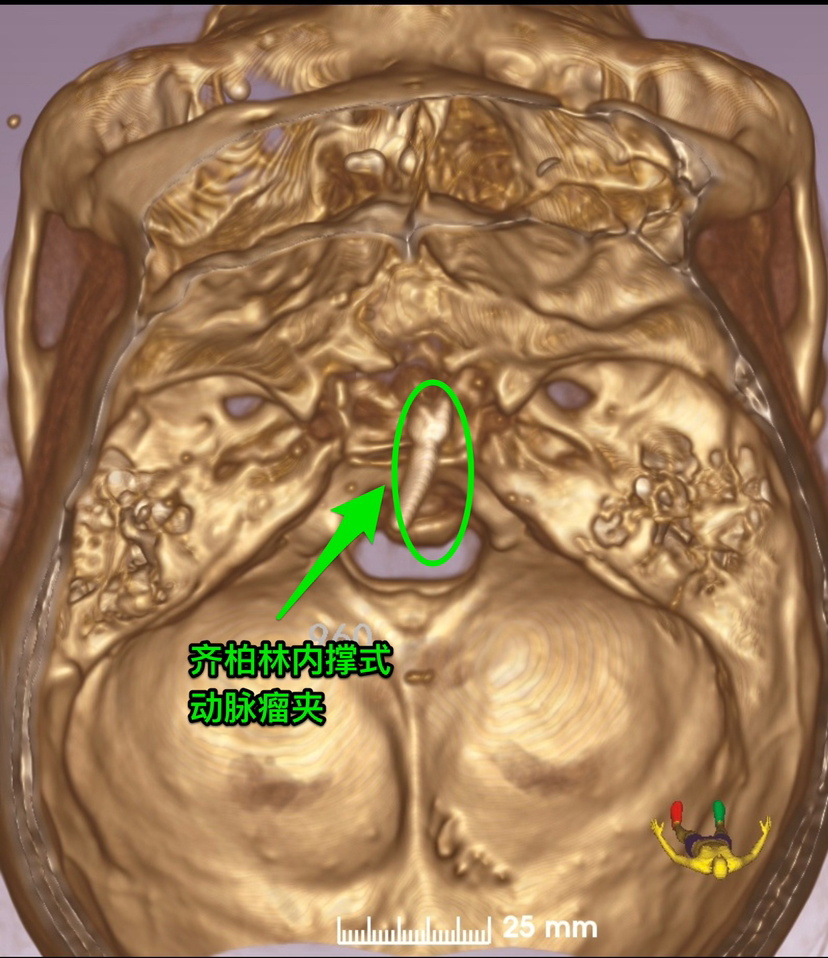

尽管患者多发动脉瘤,结合DSA显示基底动脉顶端大型动脉瘤,瘤顶部有子囊发出,磁共振显示动脉瘤顶部突入三脑室,CT显示蛛网膜下腔出血主要在三脑室、四脑室和小脑表面,判定基底动脉顶端动脉瘤是本次出血的责任动脉瘤。考虑介入治疗可能需要双支架置入,术后抗血小板治疗增加其它动脉瘤破裂出血风险,遂决定对患者进行经鼻蝶入路切除复发垂体瘤并对基底动脉顶端动脉瘤进行夹闭。

制定虚拟内镜术前计划,显示鞍背阻挡动脉瘤颈部。

术中磨除鞍背骨质